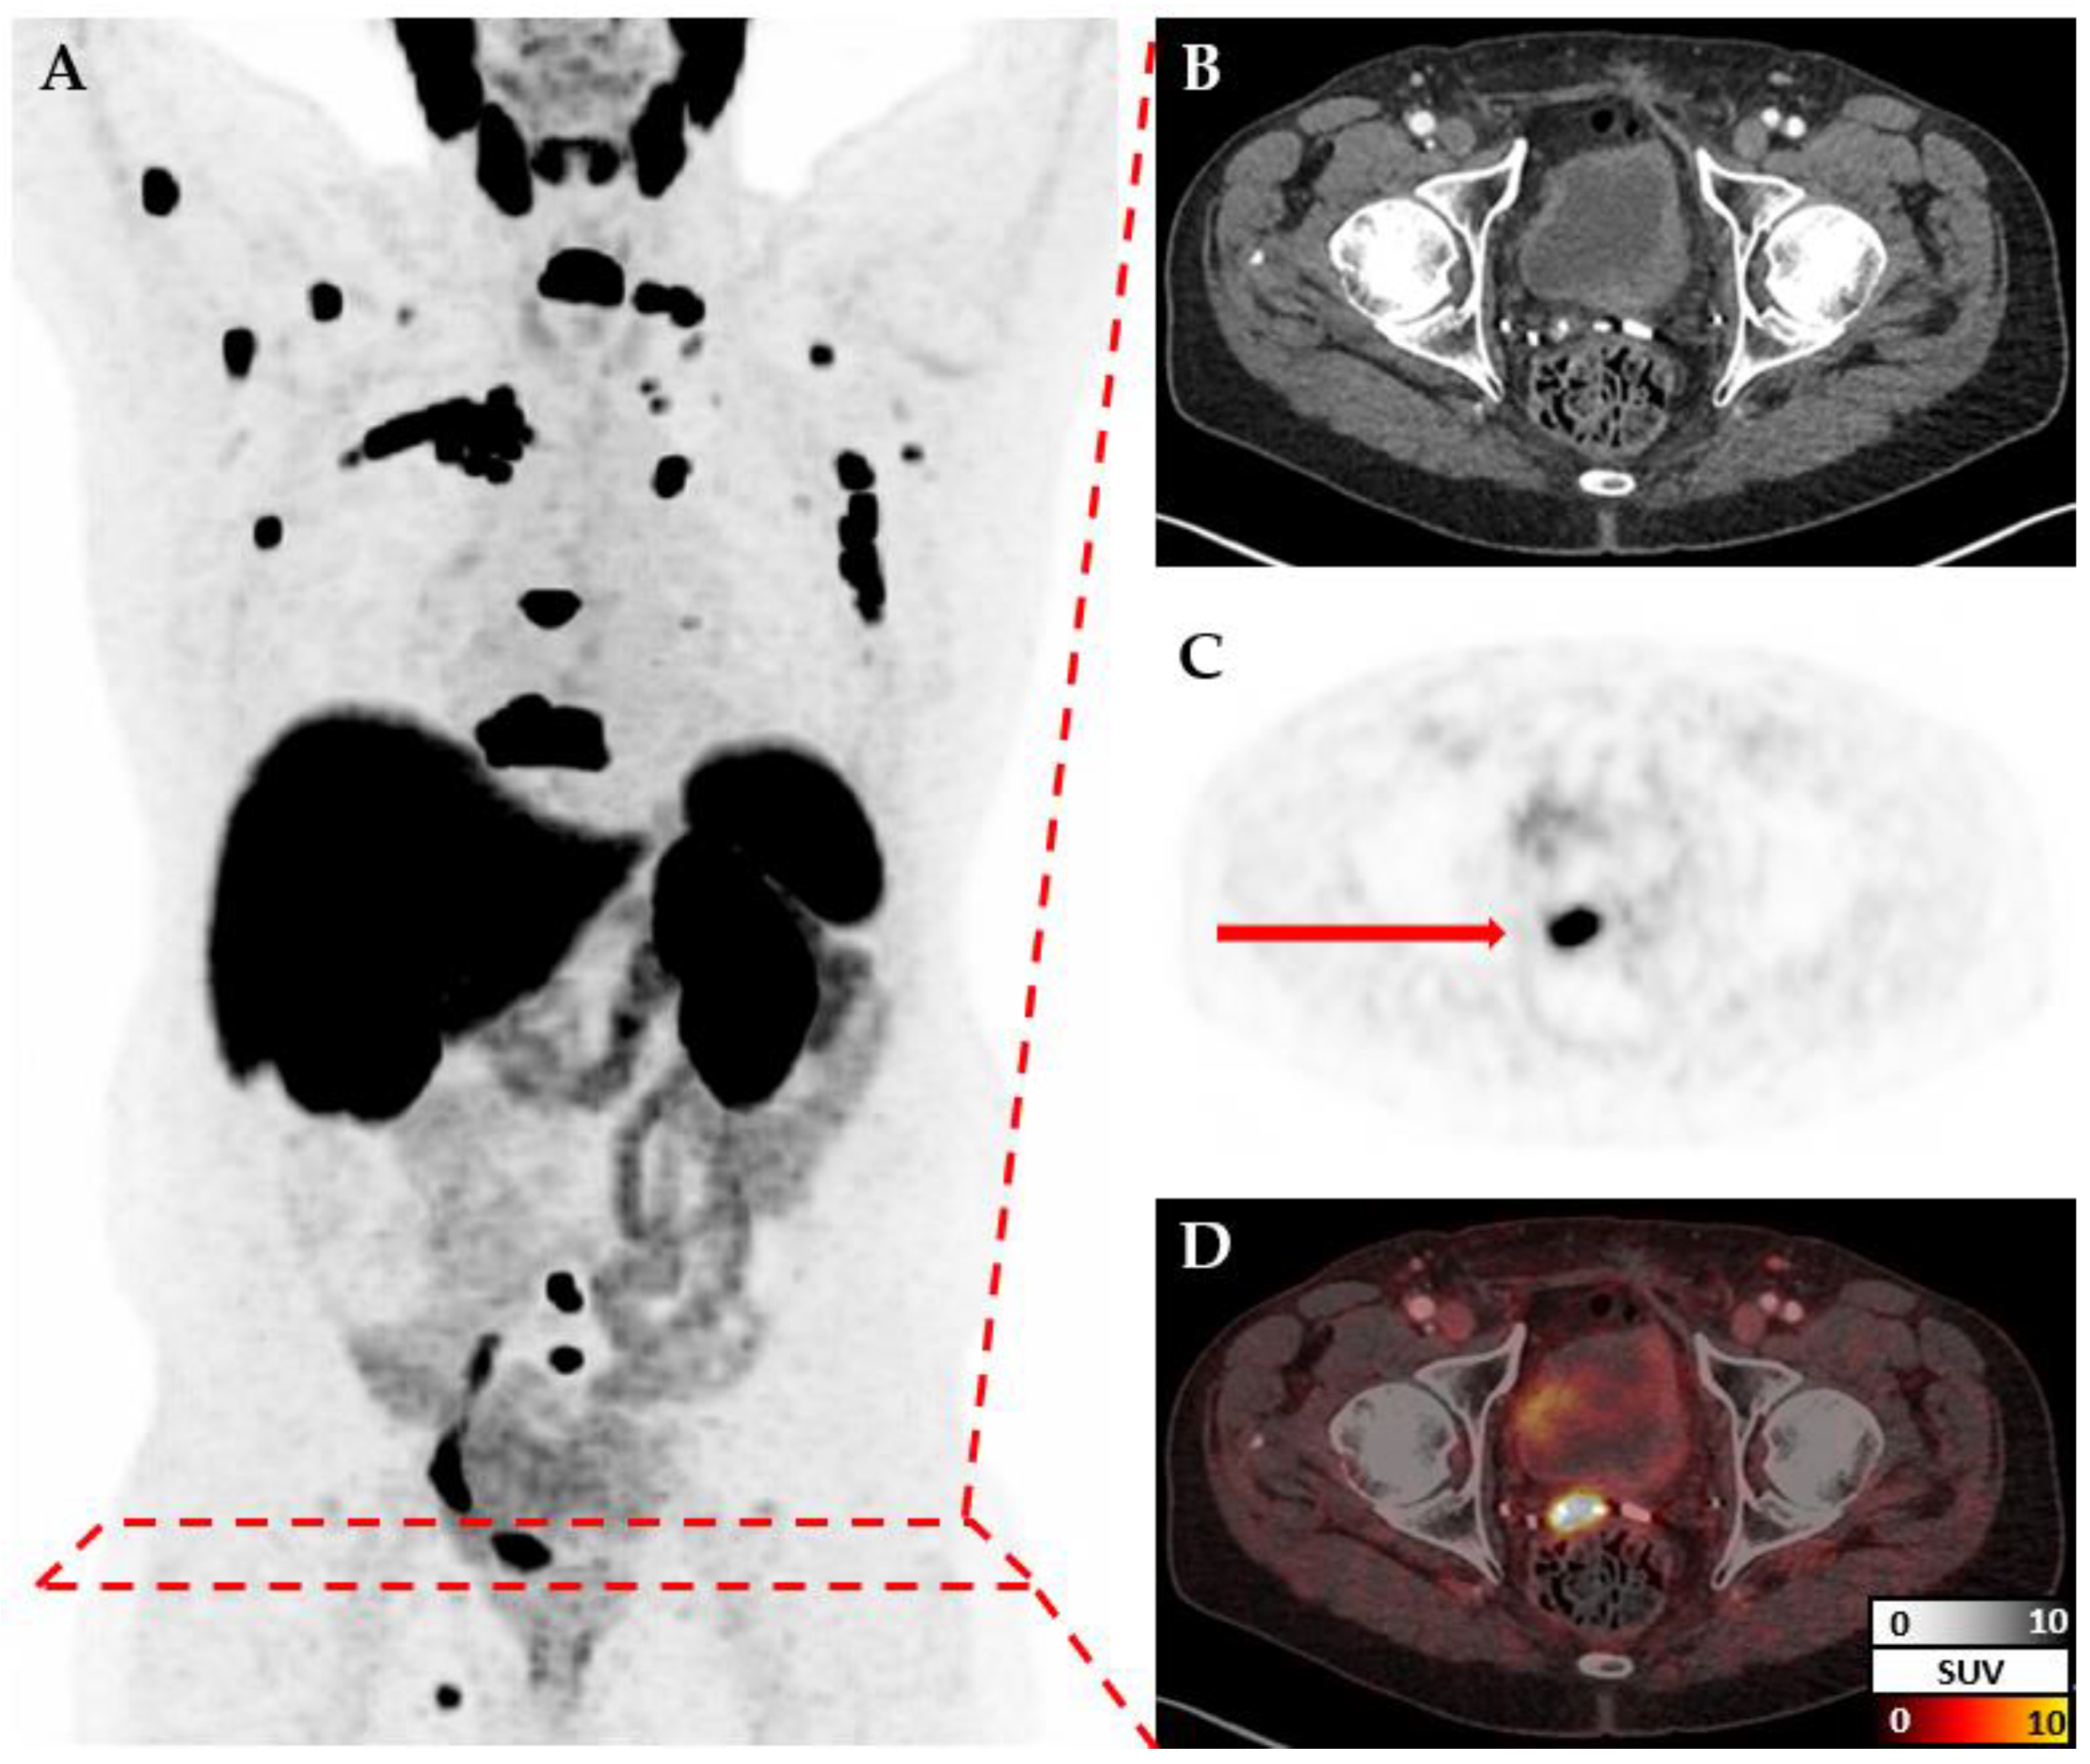

Figure 1. PSMA-PET/CT: A. maximum intensity projection; axial corresponding CT (B) and PET (C) slices; D. fused PET and CT slice. Example of a 78-year-old patient with osseus and lymphnodal metastases, as well as a local recurrence in the prostate bed (indicated by the arrow).

Images were exported from the clinic PACS in DICOM format and converted to NIfTI via dcm2niix [7]. In 59 cases, the conversion failed, so these cases were excluded. Data loaders for deep learning in Python (version 3.12.3) were implemented using nibabel (version 5.2.1, [8]), PyTorch (version 2.3.0, [9]) and Monai (version 1.3.1, [10]). CT and PET images for each patient are measured at different resolutions but cover the same volume (Figure 1). Therefore, after reading both files individually, they are re-scaled to a standard resolution of 150x150x150. Additional transformations like cropping or augmentation transformations are applied depending on the model. Metadata and labels are provided as a simple csv file and loaded via Pandas (version 2.2.2, [11,12]).